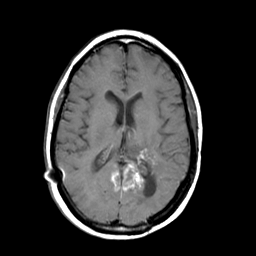

MR Study #3 -- Slice #30